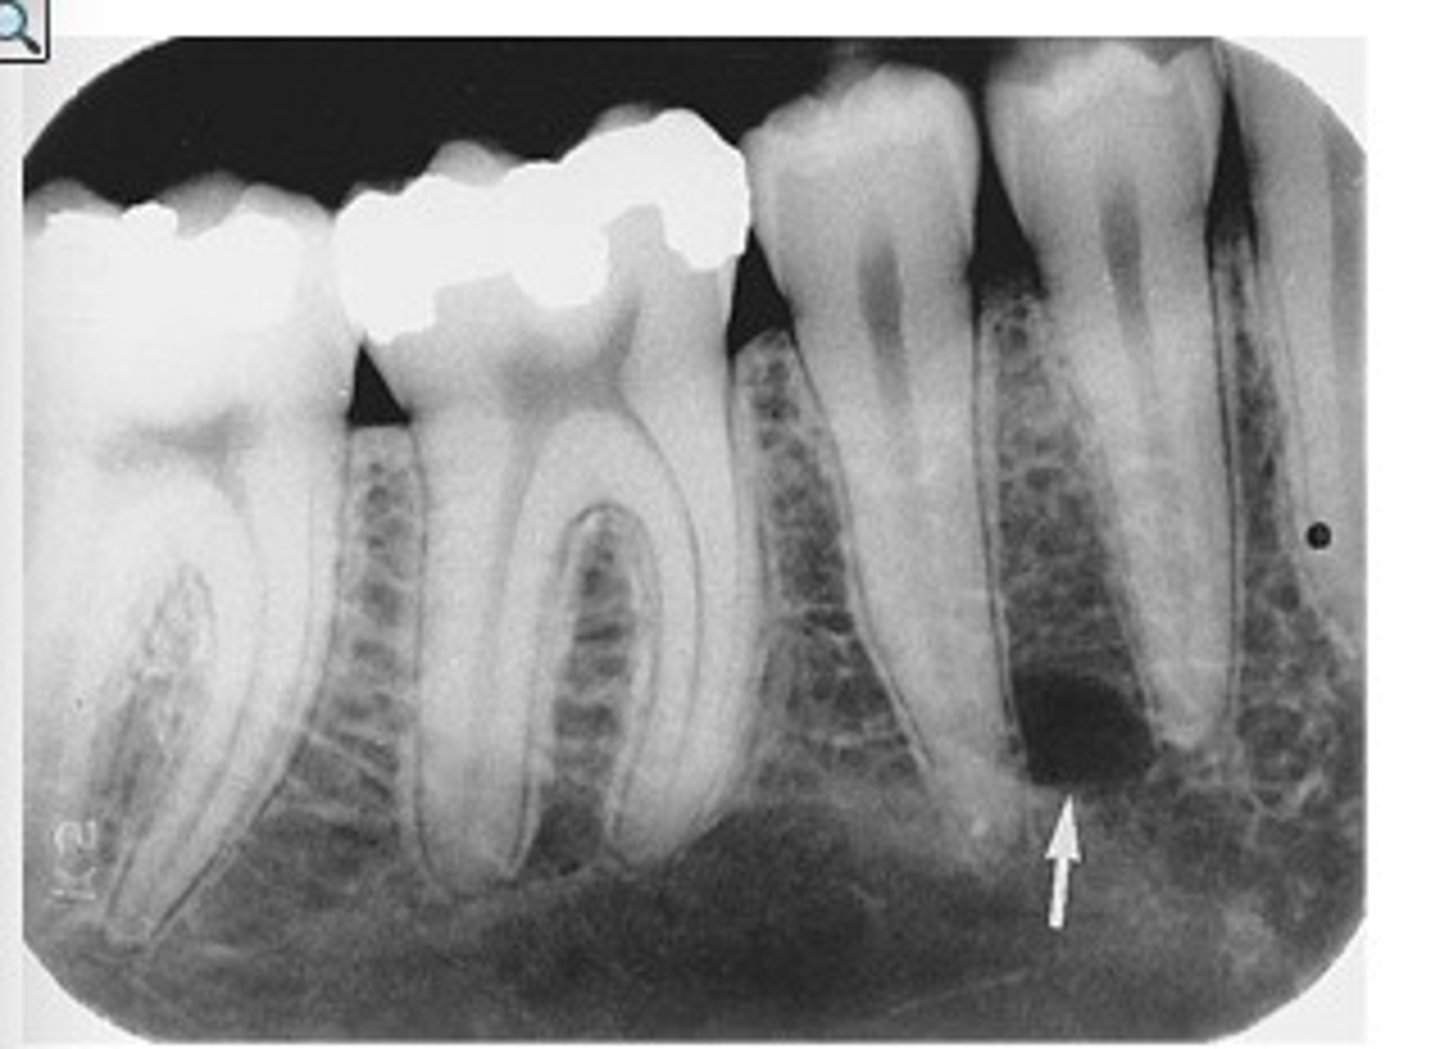

Bitewing radiograph

image view showing the crowns of both arches on one film

bitewing radiographs used to detect:

or monitor interproximal caries if the proximal surfaces of the teeth cannot be visually tactilely examined

Which image would be best utilized to see the relationship of the alveolar bone?

vertical bitewing

the most common reason for taking bitewing radiographs is to evaluate:

interproximal caries